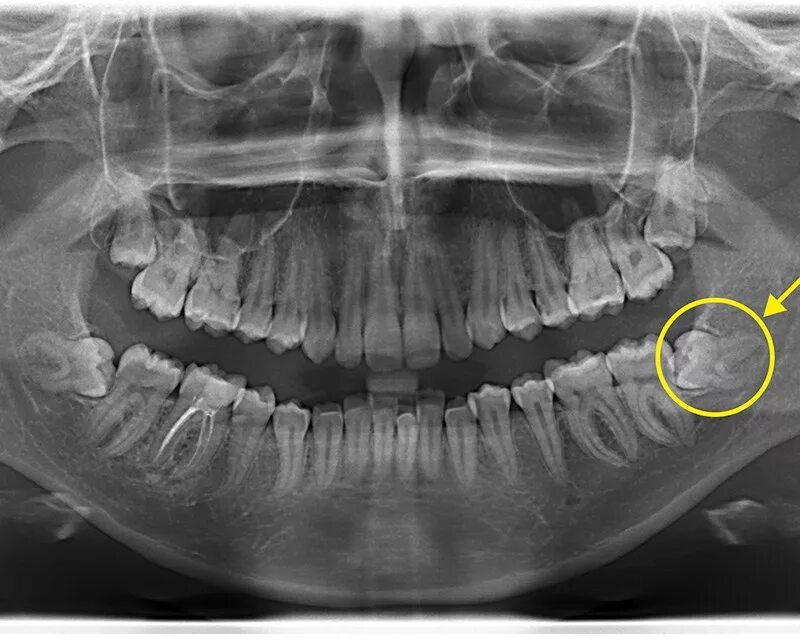

Снимок верхней и нижней челюсти